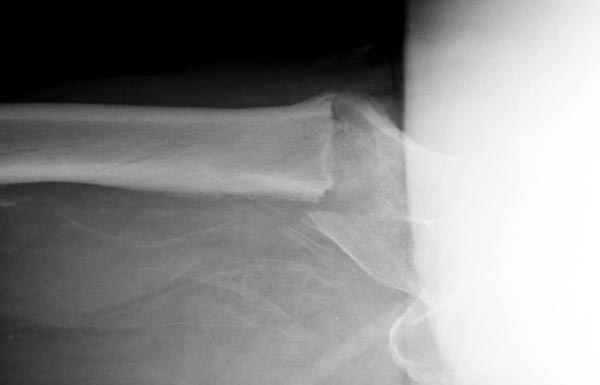

Изначально была выбрана не правильная точка введения стержня, в связи с чем в конце, я подчеркну, в конце операции произошло из-за напряжения между прокимальным концом канала бедра и стержнем разрушение в/3 бедра.

Проволока наложена потому, что при введении штифта не прошли эту зону римером и произошли сколы на концах отломков.

Под ЭОП во время операции такого смещения не было. Мы бы конечно не отпустили этого больного с такой картиной (сами бы что-то сделали или к вам отпр).